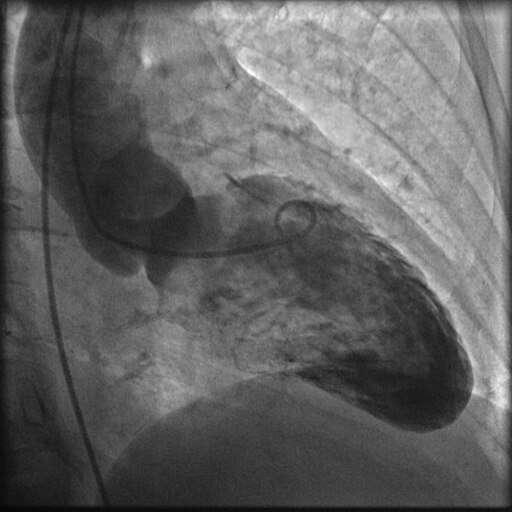

- InnovaSpin — оптимальная проекция сосуда за одну инъекцию контраста. Клиническое приложение для ротационной ангиографии Innova Spin позволяет увидеть всю камеру сердца и анатомию коронарных сосудов за одну съемку и с одной инъекцией контраста;

- Innova 3D — получение трехмерных изображений в операционной. Программное обеспечение трехмерной ангиографии Innova 3D — это режим получения трехмерных изображений из ротационной ангиографии, предоставляющий точную сосудистую визуализацию, непосредственно у операционного стола. Приложение позволяет получить трехмерную реконструкцию с высоким пространственным разрешением путем измерения спектра плотностей окружающих тканей;